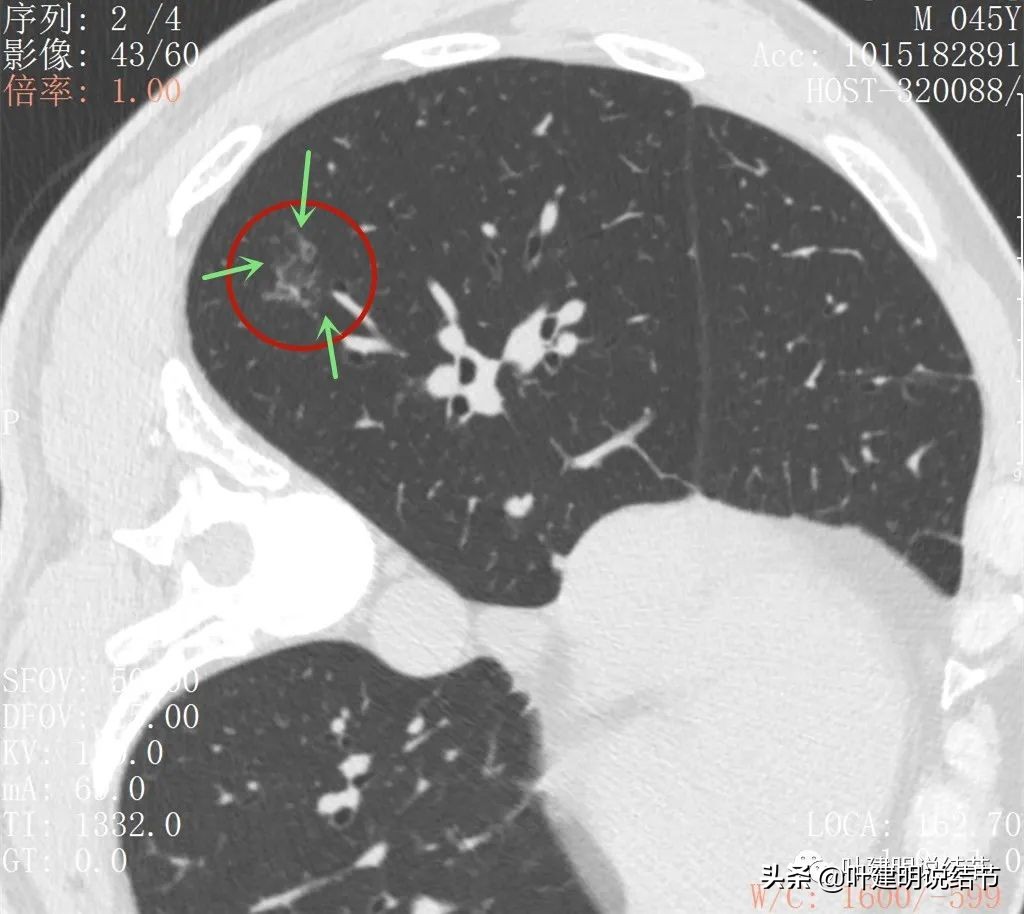

2022年5月复查靶扫描的图像:

病灶出现,磨玻璃密度,非圆形或类圆形,感觉比较散

病灶虽然不密,但轮廓较清,磨玻璃成分明显,感觉偏向恶性